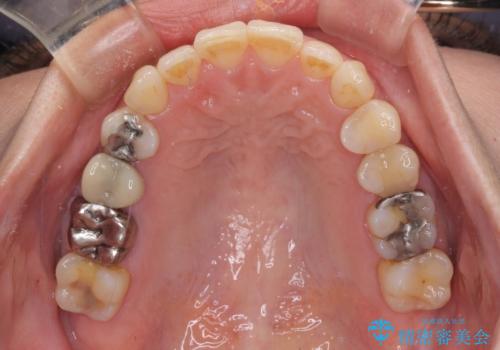

切端咬合をインビザライン矯正で解消

- 前歯のデコボコを気にして来院された患者様です。

上下前歯の先端同士が接触する切端咬合であったため、上顎は歯列を拡大し、下顎はIPR(歯と歯の間を削る)により叢生を解消しながら歯列を小さくすることとしました。

治療途中に前歯に歯髄充血を思わせる痛みが認められたため、無理のない歯の移動と頻繁な経過観察を行いました。

切端咬合はスムーズに解消され、前歯の負担を軽減させることができました。